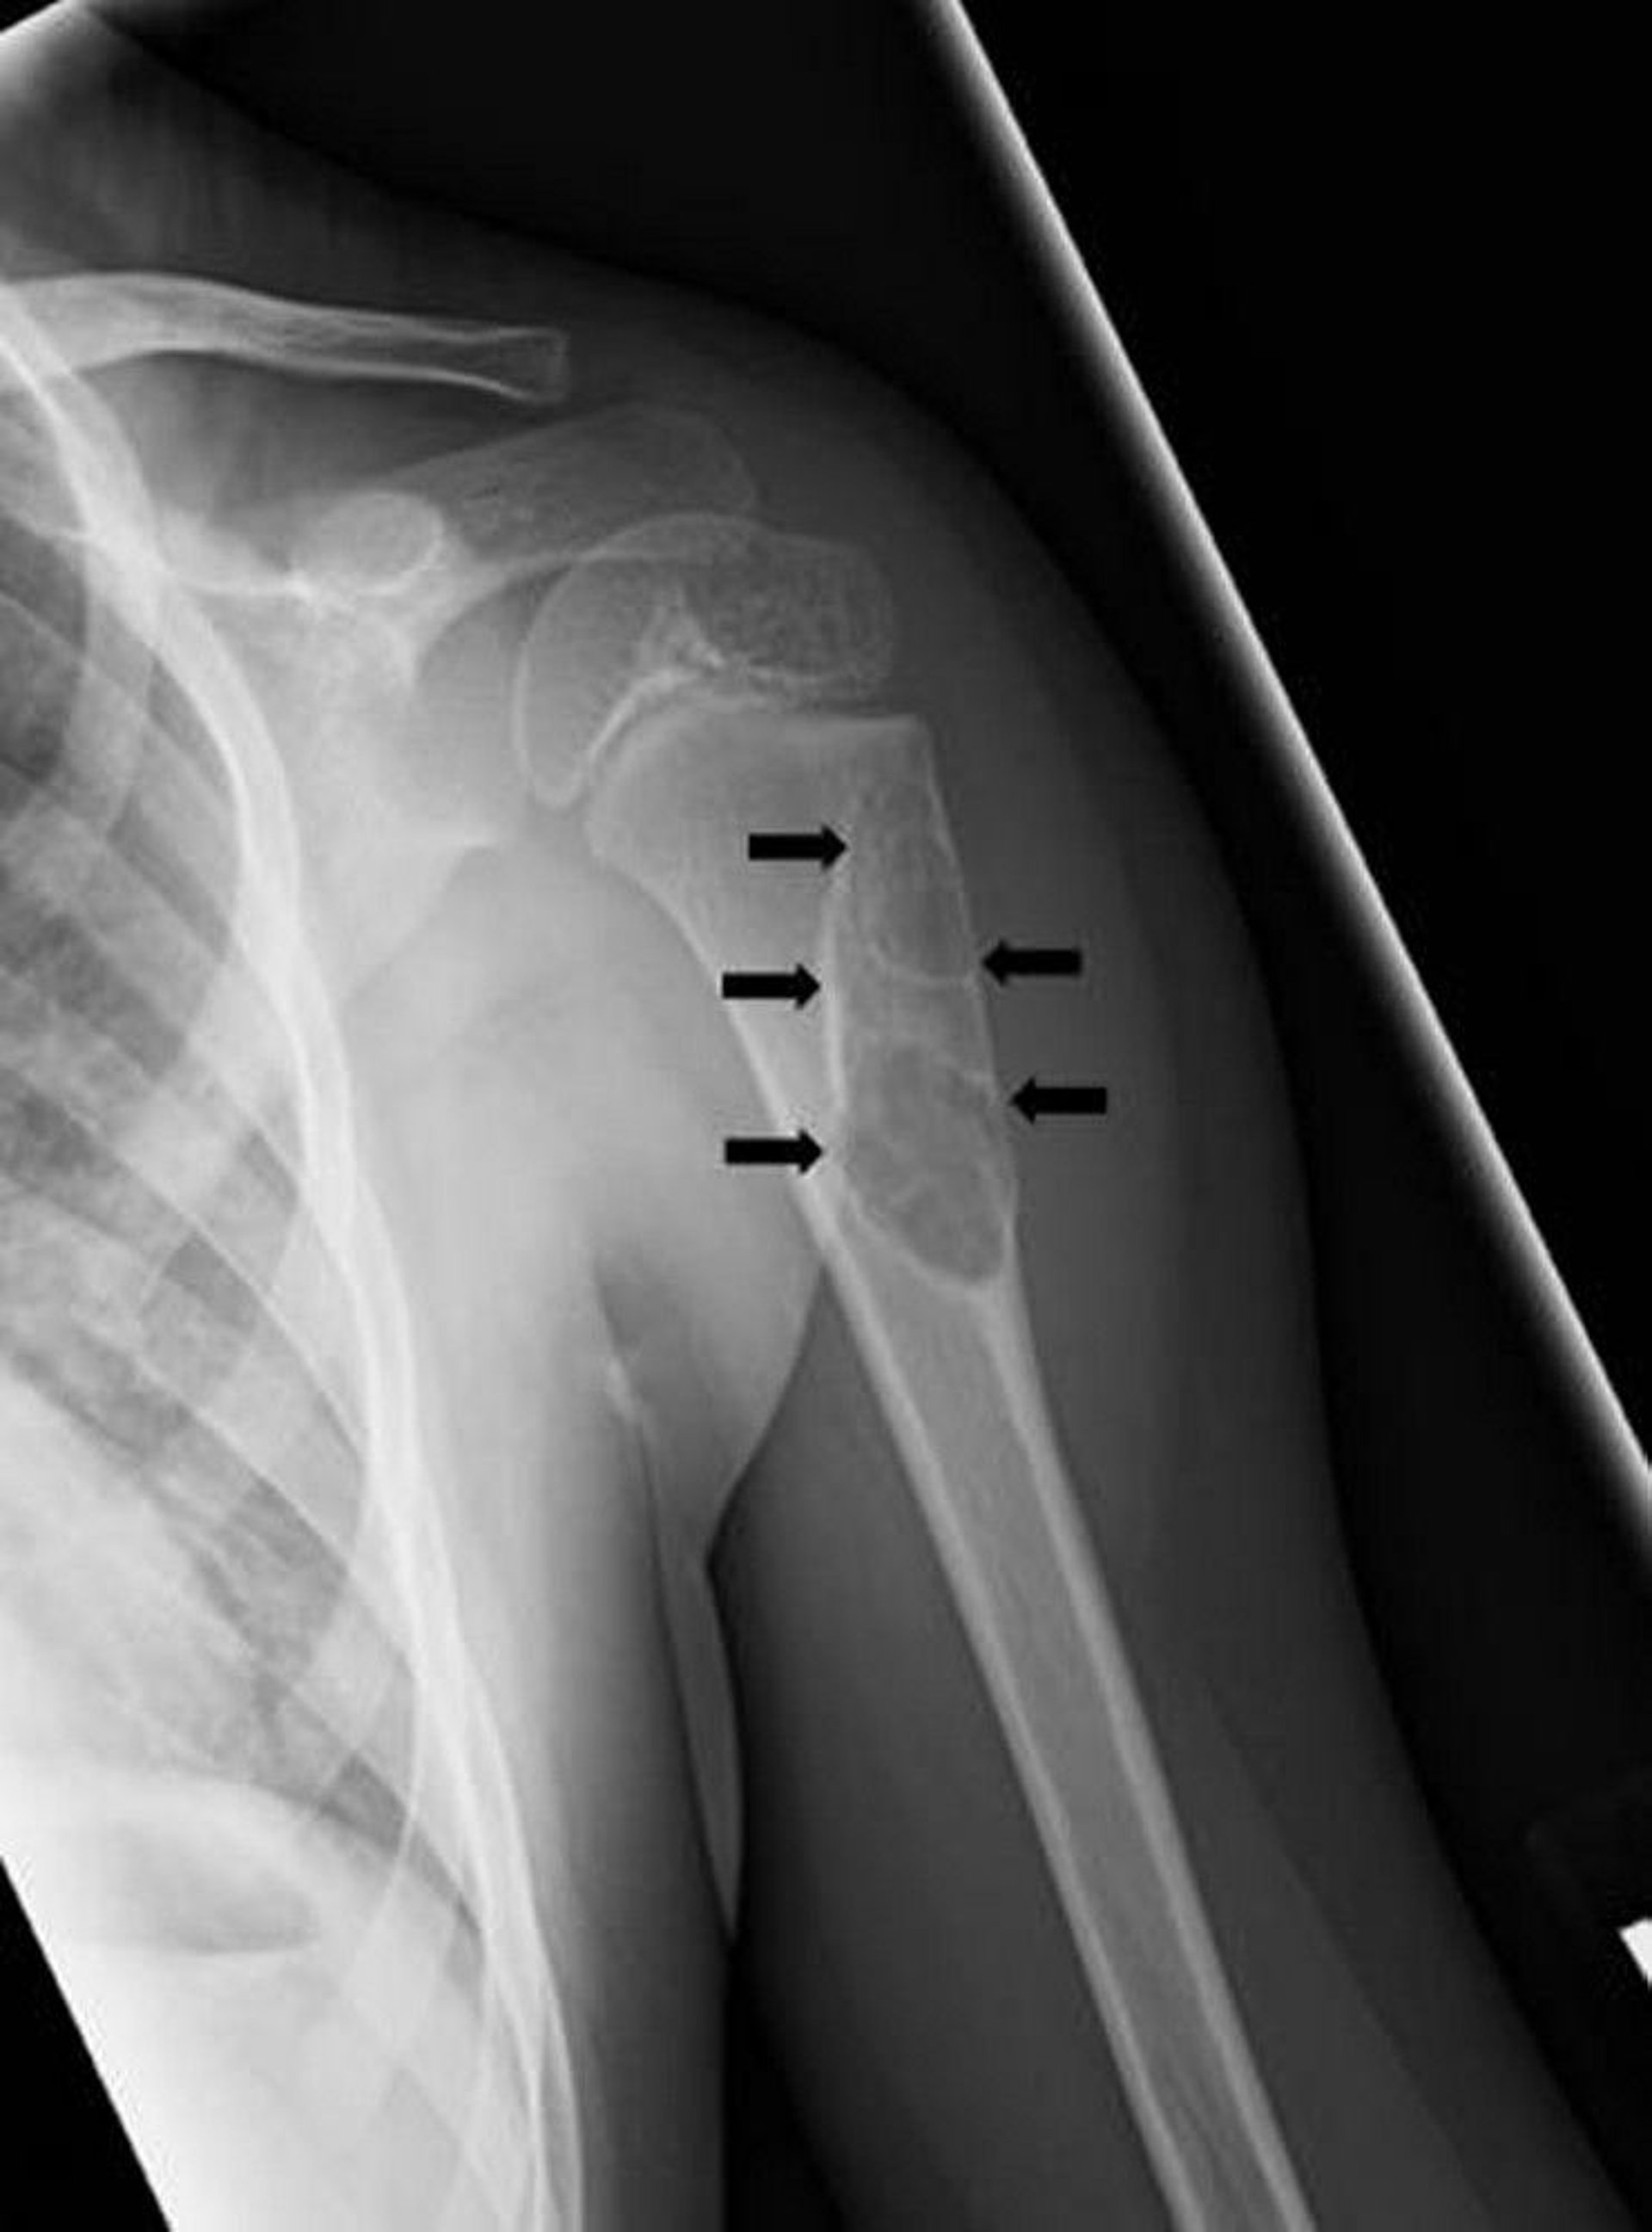

Unicameral Bone Cyst

This radiograph shows a cystic lesion (arrows) of the humerus in child consistent with a unicameral bone cyst.

Image courtesy of Michael J. Joyce, MD, and Hakan Ilaslan, MD.